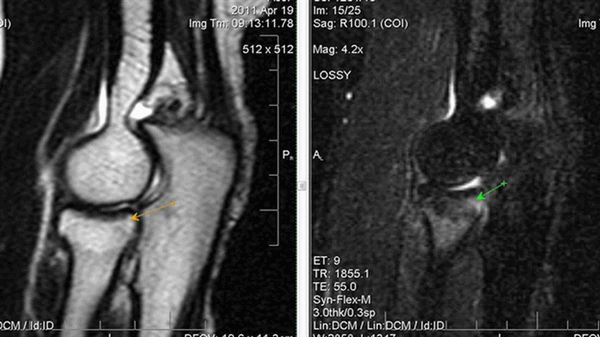

МРТ локтевого сустава в корональной плоскости. В подкожно-жировой клетчатке локтевого сустава отмечаются множественные образования неправильной вытянутой формы, местами сливающиеся между собой — вероятно, венозная мальформация.

МРТ локтевого сустава в сагиттальной плоскости. Отмечается повышенное скопление свободной синовиальной жидкости в полости локтевого сустава. Синовиальная оболочка умеренно гипертрофирована.

а) МРТ локтевого сустава в аксиальной плоскости

б)МРТ локтевого сустава в корональной плоскости. Общее сухожилие разгибателей в месте прикрепления к латеральному надмыщелку плечевой кости неравномерно утолщено, МР-сигнал от него неоднородно повышен на PD FS-ВИ и Т2-ВИ за счет выраженного отека и разволокнения (признаки латерального эпикондилита), общая целость его не нарушена. Окружающие мягкие ткани с признаками отека.